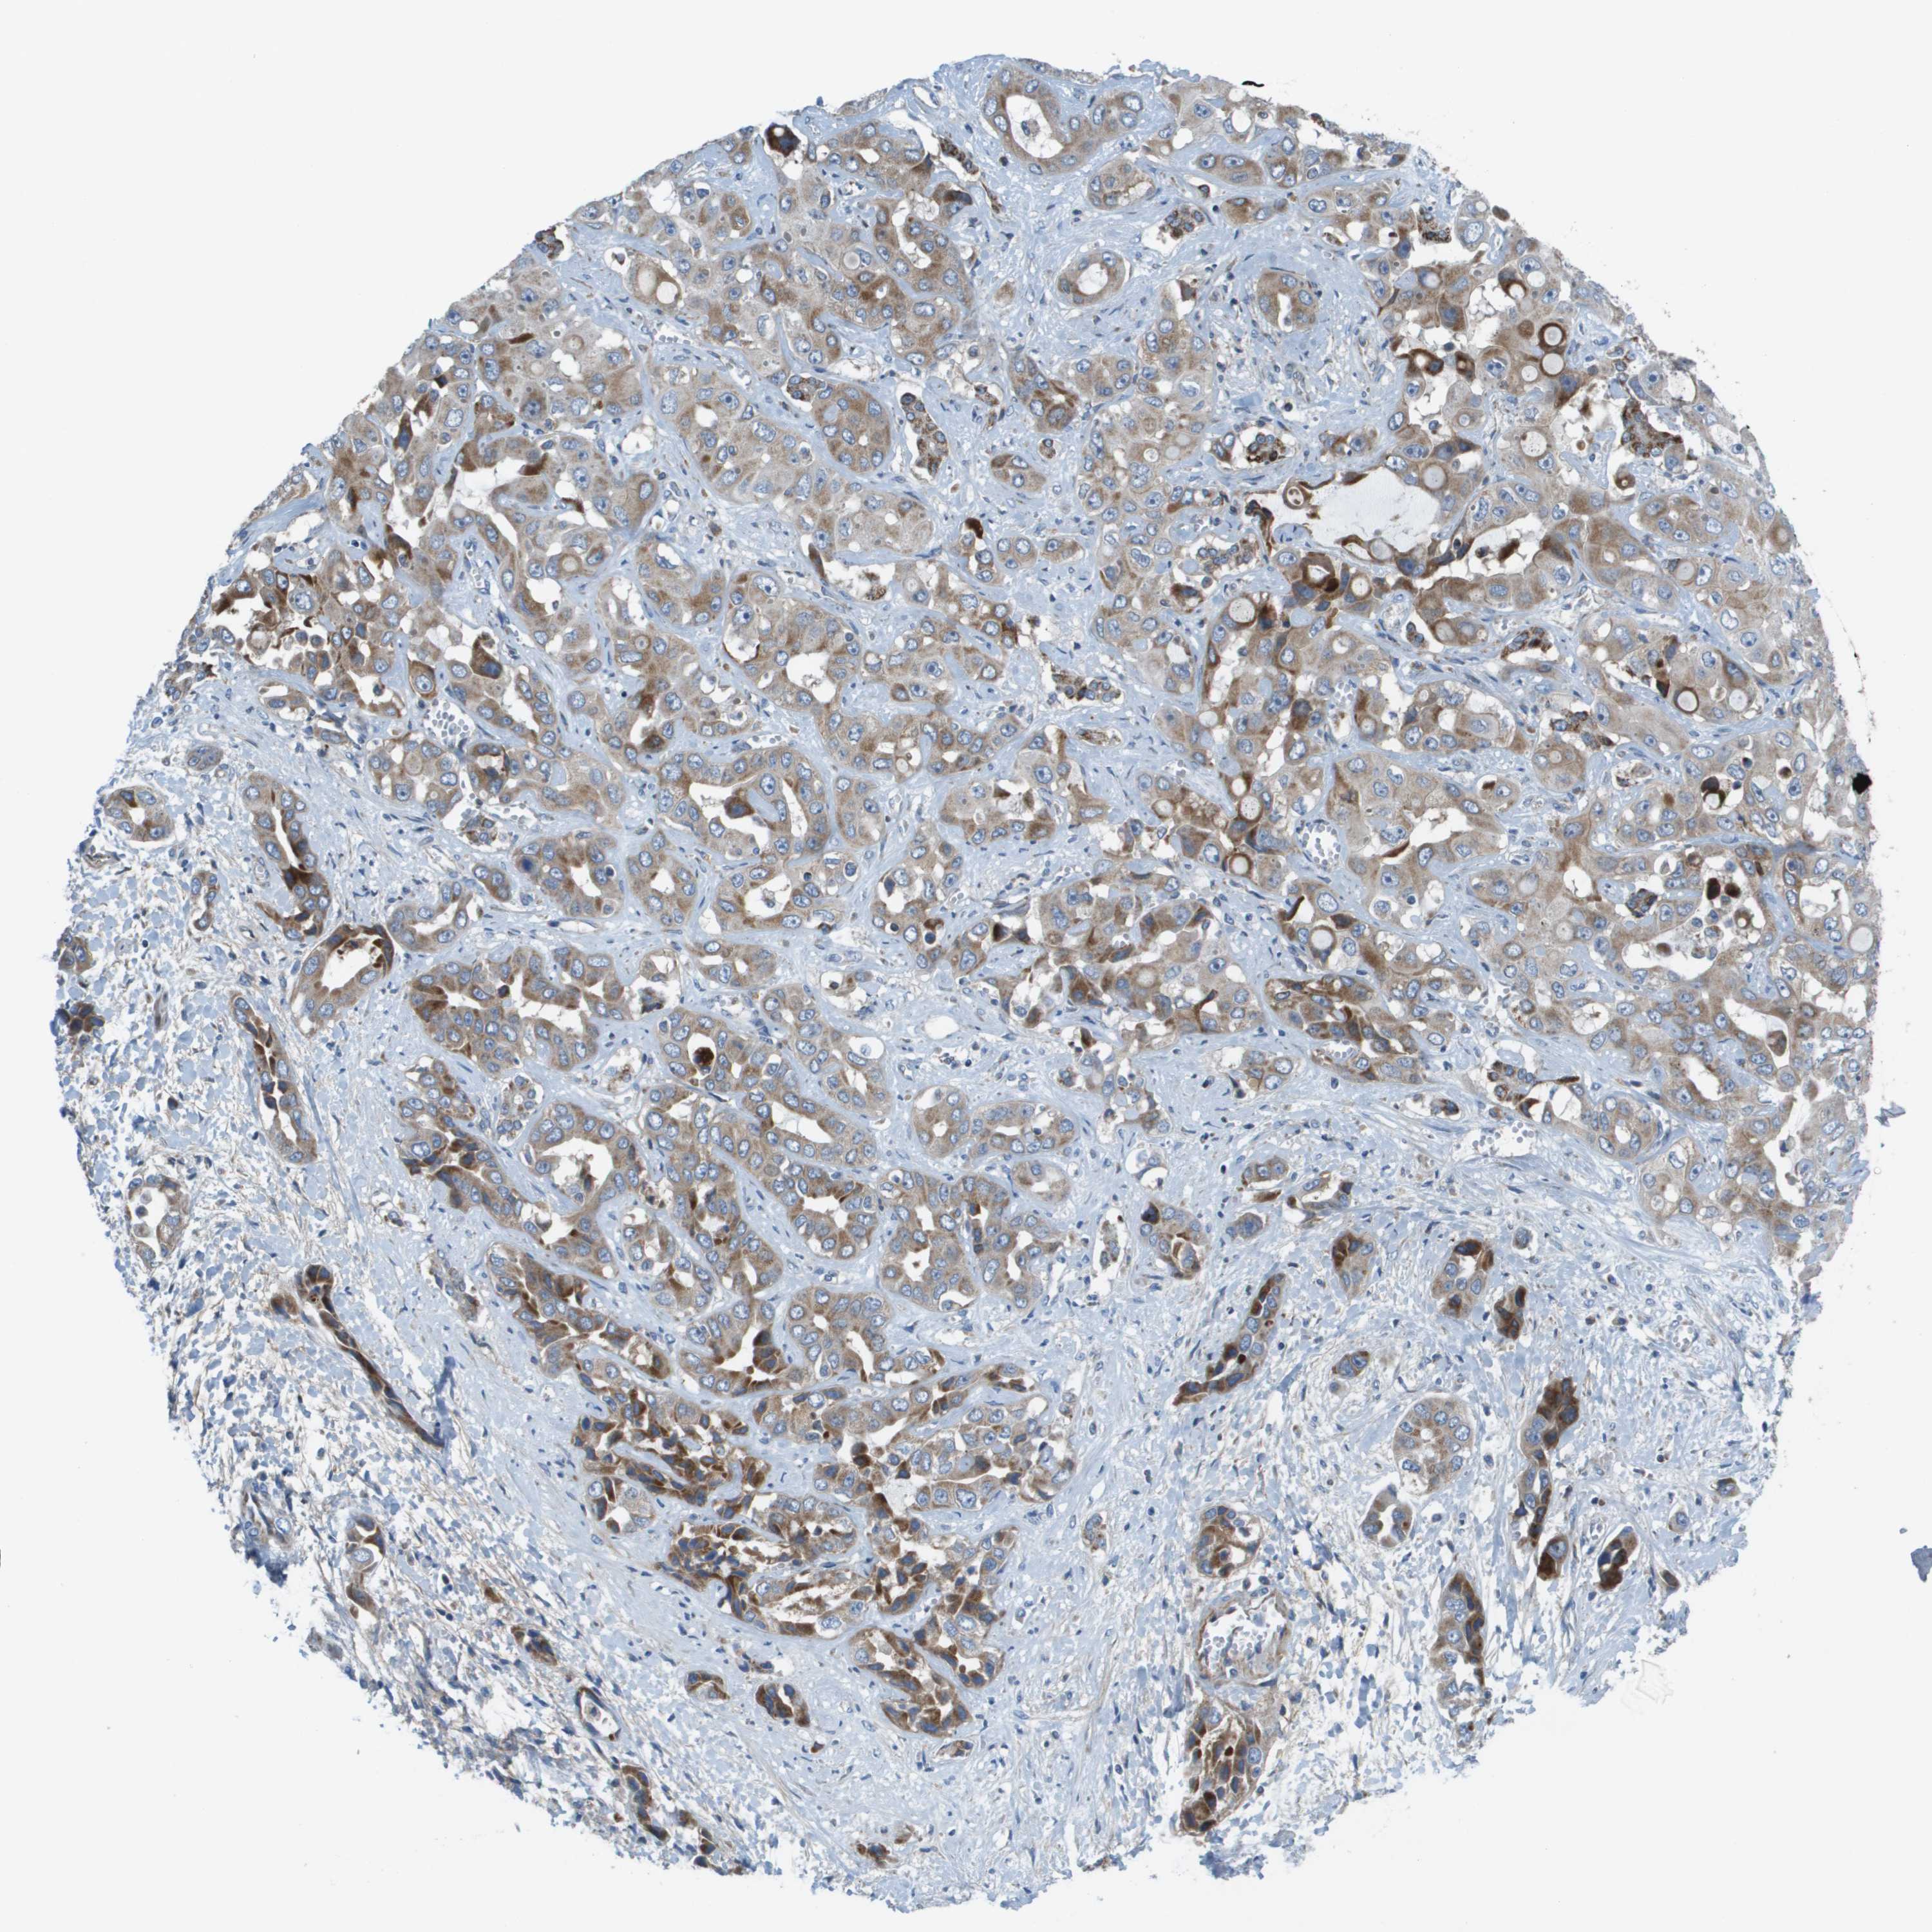

LIVER CANCER - Protein expressioni

A mouse-over function shows sample information and annotation data. Click on an image to view it in a full screen mode. Samples can be filtered based on level of antibody staining by selecting one or several of the following categories: high, medium, low and not detected. The assay and annotation is described here.

Note that samples used for immunohistochemistry by the Human Protein Atlas do not correspond to samples in the TCGA dataset.

Antibody stainingi

Antibody staining in the annotated cell types in the current human tissue is reported as not detected, low, medium, or high, based on conventional immunohistochemistry profiling in selected tissues. This score is based on the combination of the staining intensity and fraction of stained cells.

Each image is clickable and will lead to virtual microscopy that enables deeper exploration of all samples and also displays staining intensity scores, fraction scores and subcellular localization as well as patient and tissue information for each sample.

Antibody HPA011762

Antibody HPA017086

Staining

High

Medium

Low

Not detected

Intensity

Strong

Moderate

Weak

Negative

Quantity

>75%

75%-25%

<25%

None

Location

Nuclear

Cytoplasmic/membranous

Cytoplasmic/membranous,nuclear

Cholangiocarcinoma

Carcinoma, Hepatocellular, NOS